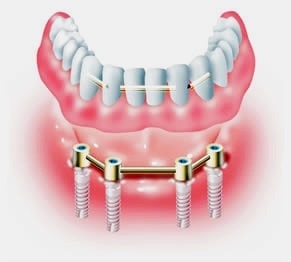

オールオン4は、奥のインプラントを骨のある部分へ斜めに埋め込み力を広く均等に分配することにより、最小4本のインプラントで全ての人工歯を支えることができる術式です。

手術による身体的負担や費用の負担なども最小限に抑えることができます。

※上顎の場合は4本で支えきれない事があり、インプラントの本数追加が必要な場合もあります。

※顎の骨の状態によっては下顎であってもインプラントの本数追加が必要な場合もあります。

被せ物はチタンフレームに組んだジルコニアを使用いたします。